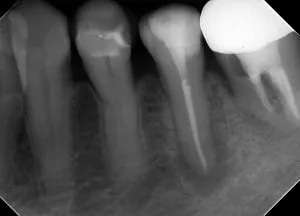

| 術前(写真) | 術後(写真) |

|---|---|

![]() |

| 術名 | 精密根管治療(一回法) |

| 年齢 | 60代 |

| 性別 | 女性 |

| 主訴 | 数ヶ月前から歯ぐきから膿が出ている(他院で歯根破折による抜歯・インプラントを宣告された) |

| 診断名 | 歯内歯周病変(根尖性歯周炎に起因するもの) |

| 治療内容 | ラバーダム防湿下での根管治療、根管充填、支台築造 |

| 治療期間 | 約9ヶ月(治療自体は1日、その後経過観察) |

| 通院回数 | 根管治療自体は1回(その他、経過観察の来院あり) |

| 費用 | 小臼歯 ¥154,000 |

| リスク・副作用 | 歯根破折の程度や歯周病の進行状況によっては、保存が不可能で抜歯が必要になる場合があります。 また、術後に一時的な痛みや違和感が生じることがあります。 |

| 補足事項 | 【診断のポイント】 CT画像にて頬側の骨吸収が確認されましたが、他部位に歯周病がないことや未処置歯(イニシャルトリートメント)であることを踏まえ、 根管治療による骨再生が可能と判断されています。 【経過】 術後1週間でフィステル(瘻孔)が消失し、9ヶ月後にはレントゲン上で骨の完全な再生が確認されました。 |